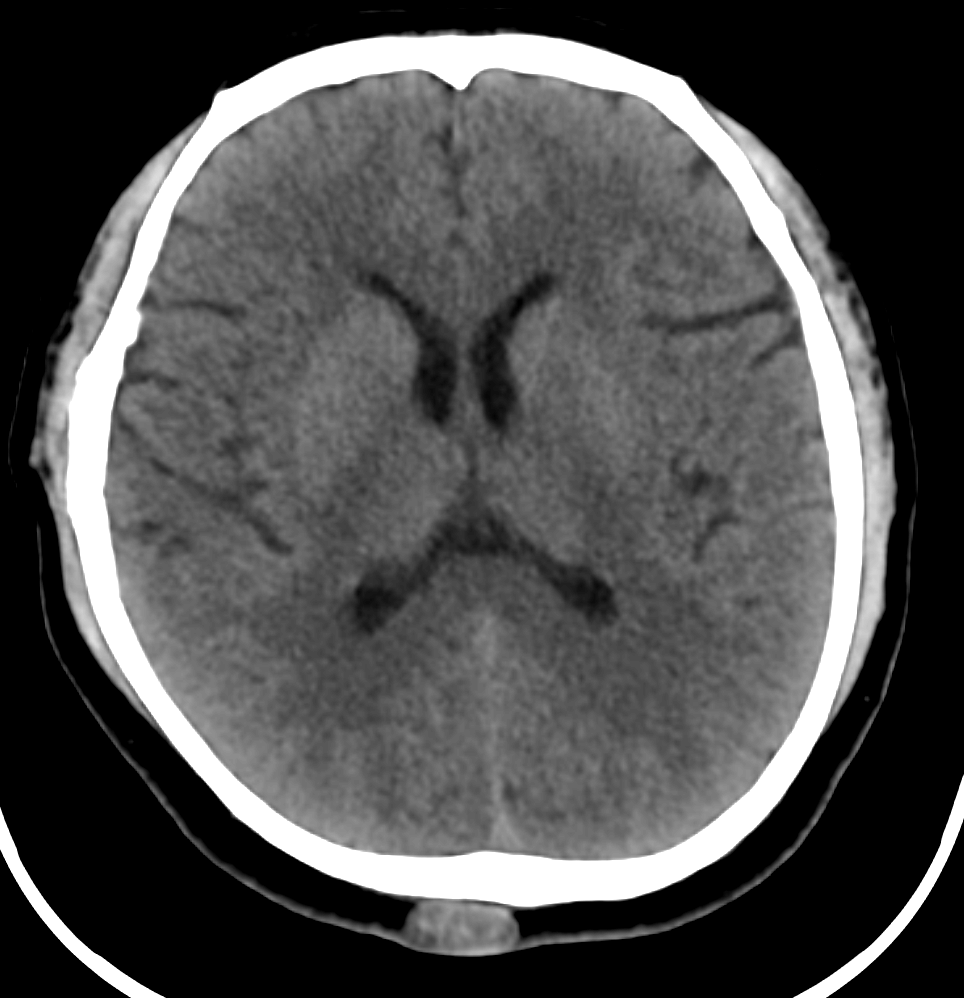

Neurological Disorders | Acute intracranial hemorrhage, skull fractures, ischemic stroke (acute phase) | Brain tumors, demyelinating diseases (e.g., multiple sclerosis), epilepsy focus localization, spinal cord pathologies |

Trauma & Emergency | Rapid assessment of polytrauma, internal bleeding, and fractures | Not suitable for acute trauma; used for soft-tissue evaluation after stabilization |